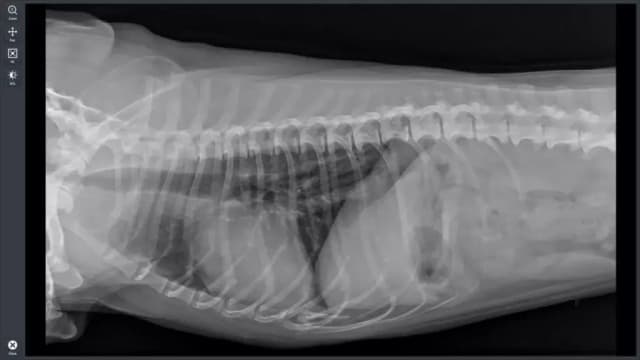

Tag jakie są ceny przeswietlenia u weterynarza